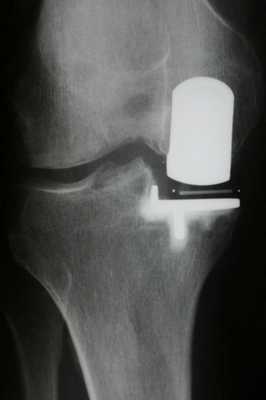

Имплант на рентгене.

Одномыщелковая замена сустава на рентгене.